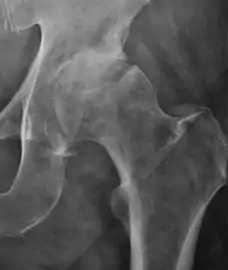

Projectional radiography ("X-ray") is the first imaging technique of choice in hip pain, not only in older people with suspected osteoarthritis but also in young people without any such suspicion. In this case plain radiography allows categorization as normal hip or dysplastic hip, or with impingement signs, pincer, cam, or a combination of both.[1]

Plain radiography allows us to categorize the hip as normal or dysplastic or with impingement signs (pincer, cam, or a combination of both). Besides these, pathologic processes like osteoarthritis, inflammatory diseases, infection, or tumors can also be identified (Figure 1).[1]

Figure 1.

Radiography in normal hip